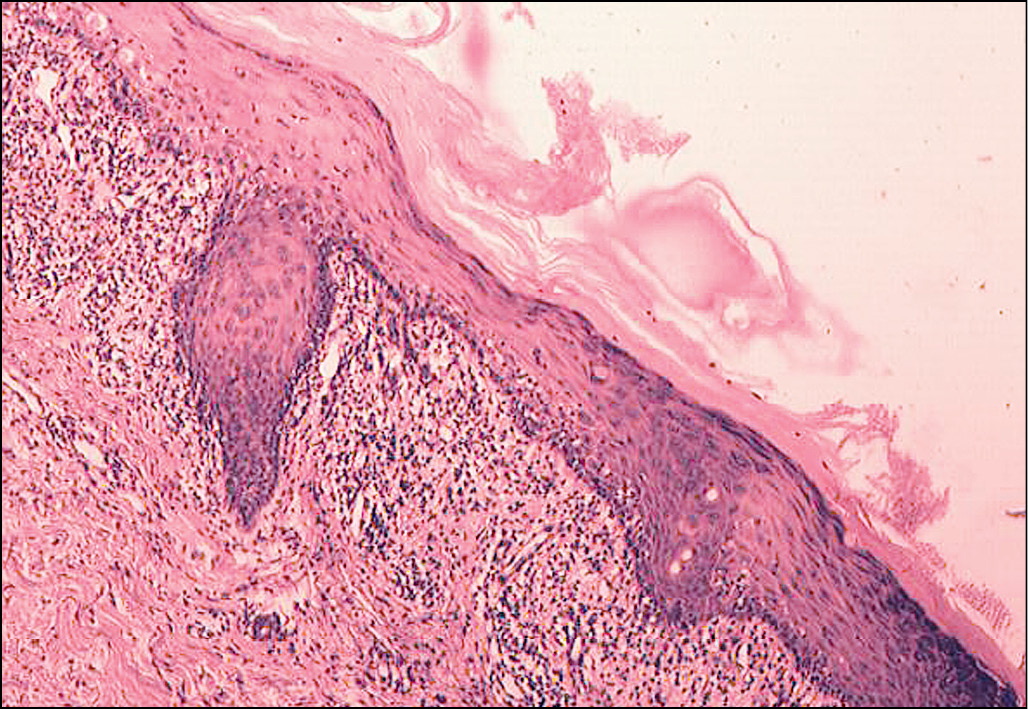

Больная Б., 60 лет, поступила с жалобами на высыпания на коже лица, шеи, плеч, верхней части груди и спины (рис. 1), которые возникли около года назад. Начало заболевания связывает с инсоляцией во время отдыха. Субъективные ощущения отсутствуют, однако при снятии чешуек с поверхности высыпаний возникает болезненность. Картина гистологического исследования представлена на рис. 2.

Рис. 2

Диагноз: дискоидная (хроническая распространённая) красная волчанка.

Гистологическое исследование. Гиперкератоз с роговой пробкой в углублении эпидермиса, вакуольная дегенерация базального слоя, отёк дермы, расширение кровеносных и лимфатических сосудов, образование лимфоцитарных инфильтратов вокруг сосудов и придатков кожи, явления васкулита.

Патогистология. Характерными для КВ гистологическими признаками являются гиперкератоз с роговыми пробками в устьях волосяных фолликулов, атрофия росткового слоя эпидермиса, вакуольная дегенерация базальных клеток, отёк и расширение сосудов сосочкового слоя дермы, лимфоцитарная инфильтрация вокруг сосудов и придатков кожи, базофильная дегенерация коллагена, отложения муцина [1, 6].